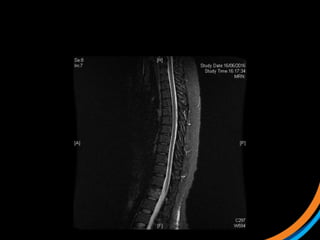

Case study 3 (Patient 009)

• 44, Female, ECOG 1

• RCC diagnosed 2007. Metastatic recurrence in 2012

• Prior RT to prevascular LN 50Gy/20# (2012)

• Started on Pazopanib, then everolimus

• Recent MRI spine shows met involving T3 and L1 vertebral body, with

involvement of superior endplate (L1)

 1) Review the images

 2) Target the lesion

T3 lesion

L1 lesion

Case study 3(Patient 009) • 44, Female, ECOG 1 • RCC diagnosed 2007. Metastatic recurrence in 2012 • Prior RT to prevascular LN 50Gy/20# (2012) • Started on Pazopanib, then everolimus • Recent MRI spine shows met involving T3 and L1 vertebral body, with involvement of superior endplate (L1)  1) Review the images  2) Target the lesion

• #35 Pre-treatment PET showing very avid disease in anterior vert body

• #38 Post RT PET at 7m The treatment effect is likely a combination of PDL1 and SBRT